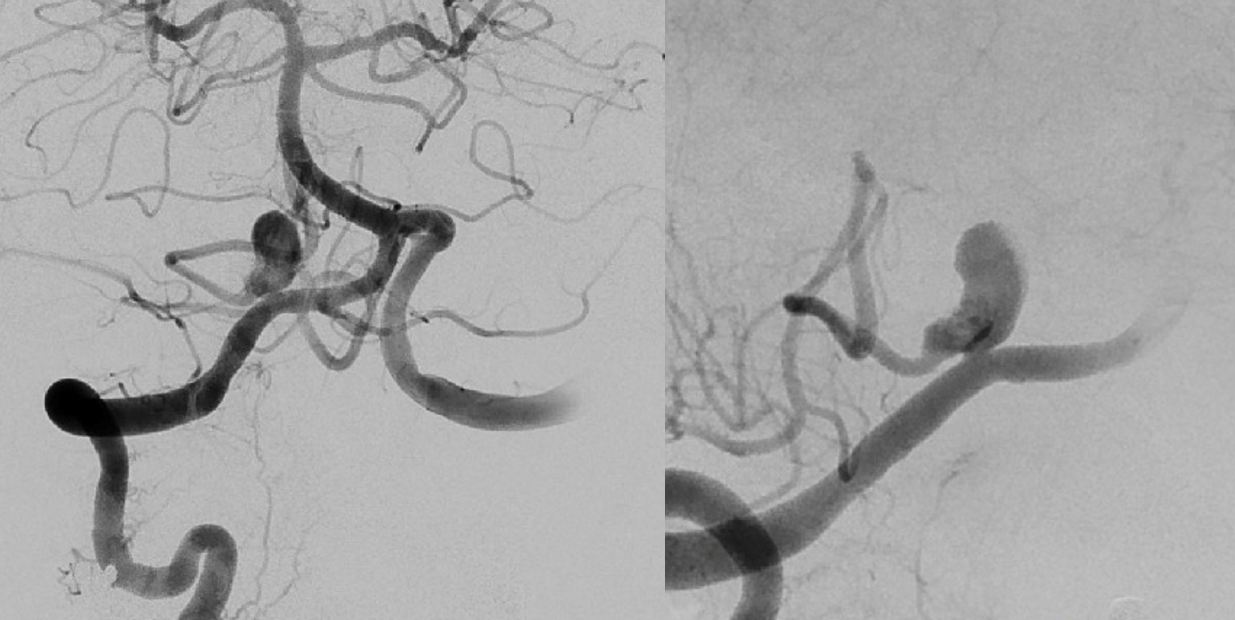

PLan to sacrifice right vert and Pipe across VB junction into PICA.

Angio